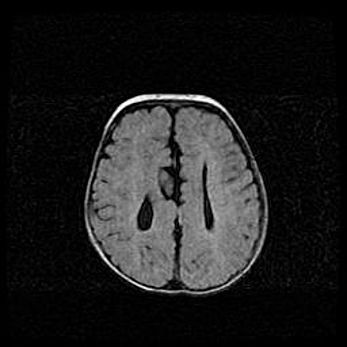

Множественные кисты обоих полушарий головного мозга, наибольшая из них в правой затылочной области. Ассиметричная атрофическая гидроцефалия.

Возраст: 7 месяцев

Вес: 5660 г

Пол: мужской

Окружность головы: 41,5 см

Срок гестации: 28-29 недель

Кисты головного мозга развиваются в результате многоочаговых некрозов вещества мозга и возникают вследствие перенесенной перинатальной инфекции, менингитов, энцефалитов, асфиксии, родовой травмы, расстройств мозгового кровообращения различного генеза. Образованию кист в веществе головного мозга плодов и новорожденных способствуют такие факторы, как высокое содержание в нем воды, недостаточная (или отсутствие) миелинизация и слабая астроглиальная реакция на повреждение.

Кисты могут сочетаться с гидроцефалией и другими поражениями головного мозга.